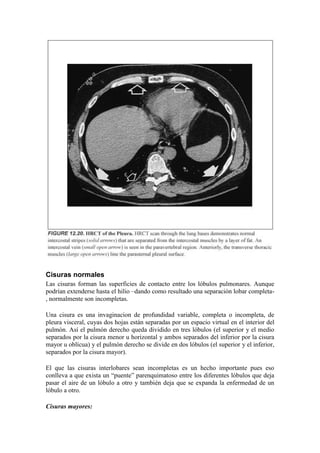

los espacios intercostales entre las costillas adyacentes. Esta “banda intercostal”

representa la combinación de las dos hojas pleurales, la fascia endotorácica y la porción

más interna del músculo intercostal. Esto lo podemos ver en el siguiente esquema.